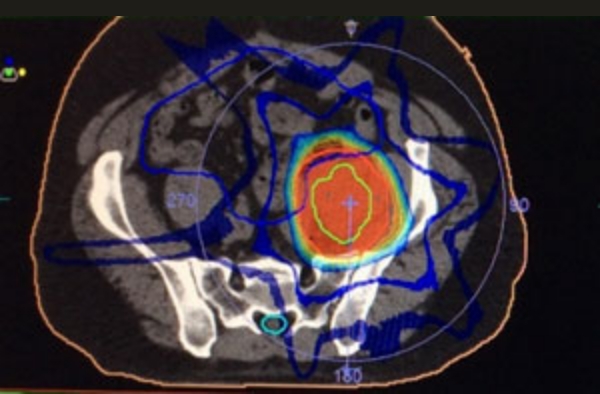

腹部リンパ節転移

他院からのご紹介例